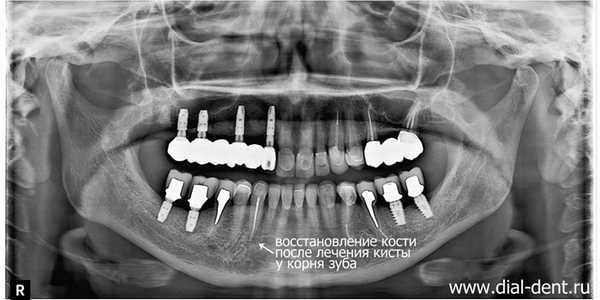

Проблема: пациентке «Диал-Дент» сделали компьютерную томограмму зубов, так как планировалась имплантация зубов. На КТ зубов обнаружена киста зуба на нижней челюсти, которая никак не проявлялась, и пациентка даже не догадывалась, что у корней зуба происходит воспаление, результатом которого может стать потеря зуба.

Достаточно часто по результатам КТ зубов выявляются проблемы, о которых пациент даже не догадывался. В данном случае КТ зубов сделано перед установкой имплантов. На КТ зубов обнаружено воспаление у корней, которое со временем могло привести к расшатыванию зуба и его потере. Пациентка даже не помнила, что этот зуб когда-то болел. В данный момент ничего не беспокоило, и только внимательность стоматолога-ортопеда С.В. Цукора помогла вовремя заметить проблему. В «Диал-Дент» перед протезированием зубов всегда делают полную компьютерную томограмму, чтобы видеть состояние всей полости рта и не упустить бессимптомные заболевания, которые могут снизить качество протезирования.

На КТ зубов, выполненной через 6 месяцев после лечения кисты зуба видно, что кость около корня восстановилась, никаких признаков кисты больше нет: